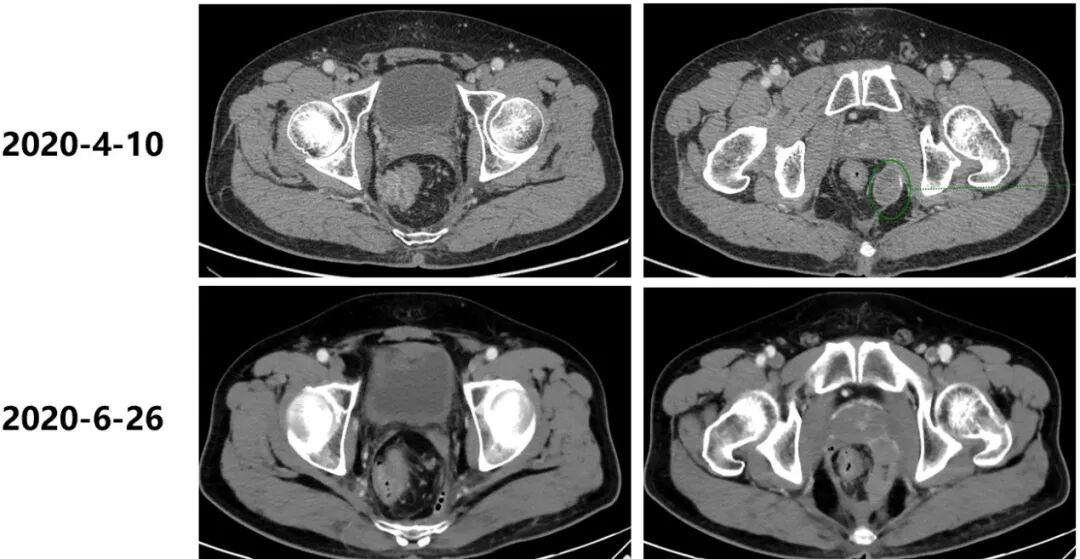

2020年4月10日至2020年10月10日,给予二线第1-10周期FOLFIRI方案化疗联合贝伐珠单抗靶向治疗,2020年6月26日,9月7日,两次疗效评估为SD。

2020年11月20日,再次腹盆腔CT增强:“直肠癌术后+前腹壁造瘘术”后改变,局段直肠壁增厚伴邻近筋膜增厚、腹膜反折处结节样增厚,需考虑肿瘤复发可能,较前片(2020年9月7日)略有进展,较前片(2020年4月10日)明显进展。疗效评估为疾病进展(PD)。